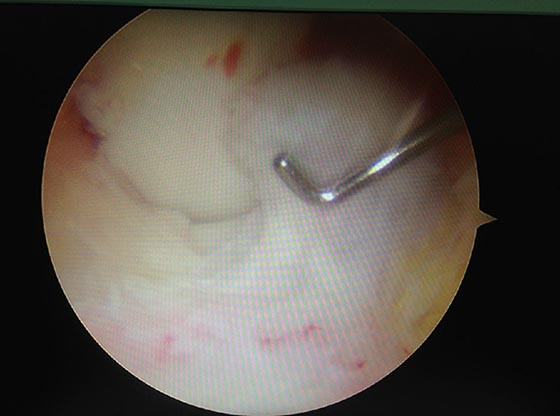

關(guān)節(jié)鏡微創(chuàng)手術(shù)

關(guān)節(jié)鏡手術(shù)是一種微創(chuàng)手術(shù),可以直接觀察到關(guān)節(jié)內(nèi)部的結(jié)構(gòu)。關(guān)節(jié)鏡不僅用于疾病的診斷,而且已經(jīng)廣泛用于關(guān)節(jié)疾病的治療。開始主要應(yīng)用于膝關(guān)節(jié),后相繼應(yīng)用于髖關(guān)節(jié),肩關(guān)節(jié),踝關(guān)節(jié),肘關(guān)節(jié)及手指等小關(guān)節(jié)等。

關(guān)節(jié)鏡手術(shù)可治療關(guān)節(jié)內(nèi)各種炎癥.如骨性關(guān)節(jié)炎滑膜炎、創(chuàng)傷性關(guān)節(jié)炎、類風(fēng)濕性關(guān)節(jié)炎、結(jié)核性關(guān)節(jié)炎、化膿性關(guān)節(jié)炎,剝脫性骨軟骨炎等,以及滑膜軟骨瘤?。惑x骨軟化癥;骨贅(骨刺),游離體,滑膜皺壁,關(guān)節(jié)紊亂癥,半月板損傷,關(guān)節(jié)囊粘連,各種關(guān)節(jié)內(nèi)骨折,各部關(guān)節(jié)粘連及關(guān)節(jié)活動(dòng)受限,各種不明原因的關(guān)節(jié)痛。